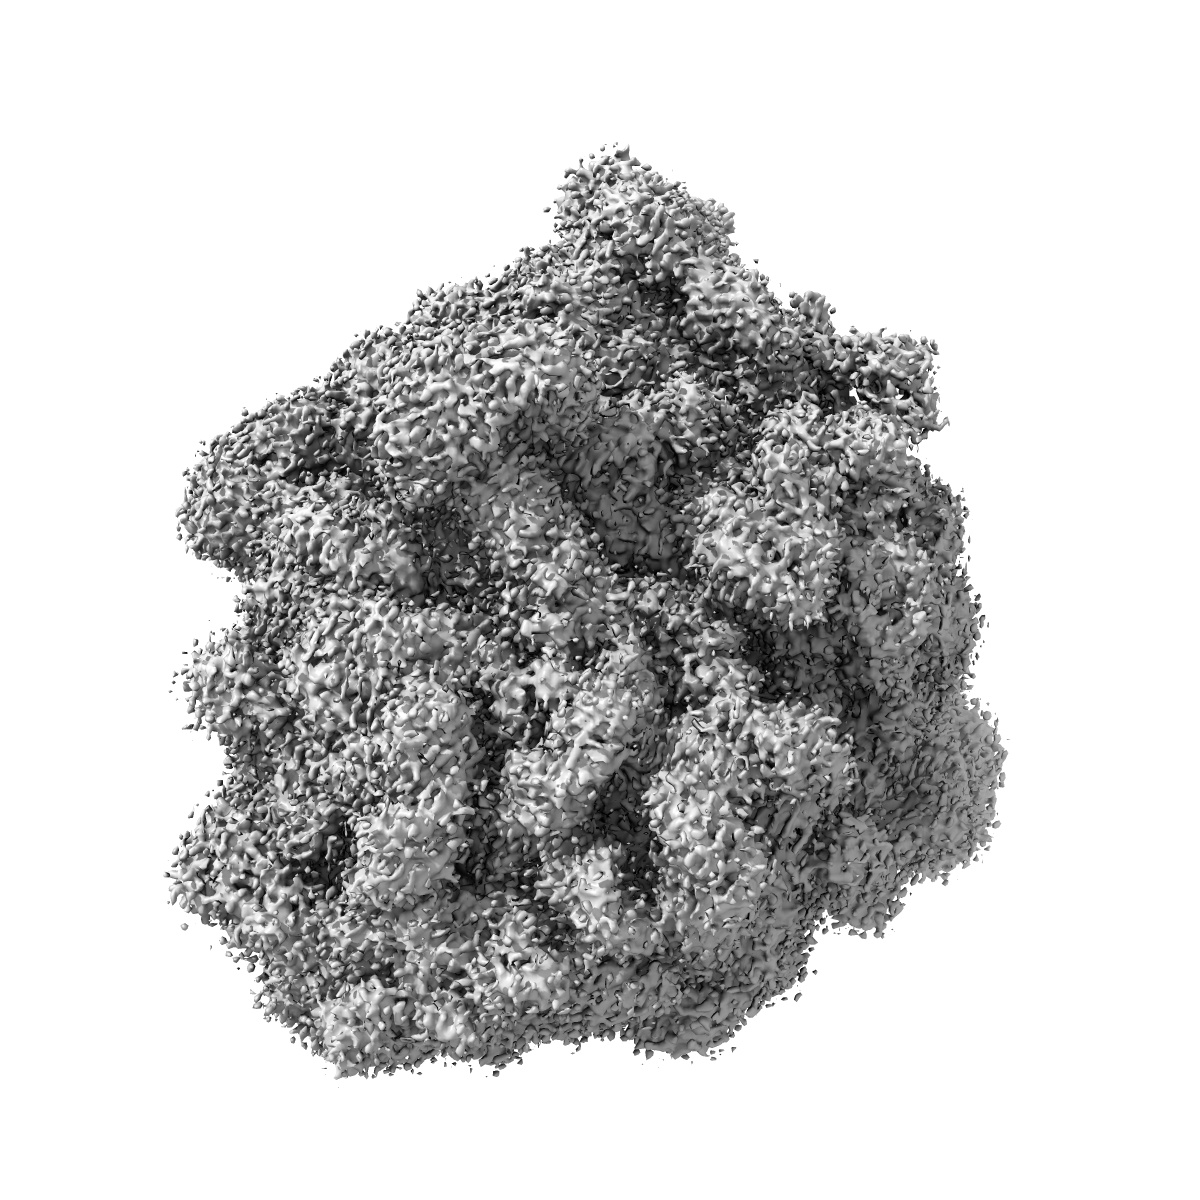

Pseudomonas aeruginosa 70s ribosome from a clinical isolate

Single-particle

3.34 Å

Structure ofPseudomonas aeruginosaribosomes from an aminoglycoside-resistant clinical isolate.

PUBMED: 31611393